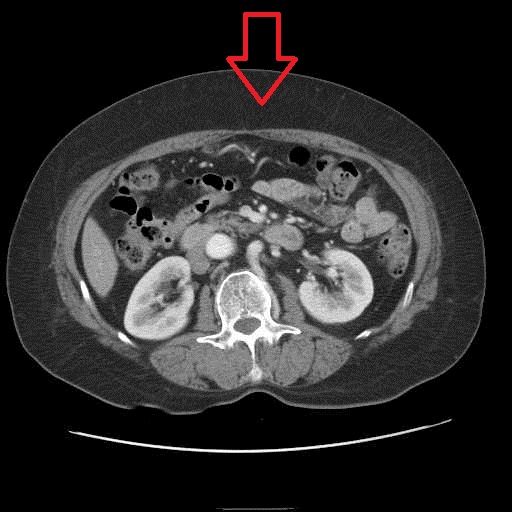

| 피하지방은 매우 얇으나, 장기 사이의 내장 비만(화살표)이 매우 심한 것을 볼 수 있다. | 내장지방은 적으나, 복벽 아래 피하지방(화살표)이 매우 심한 것을 볼 수 있다. |